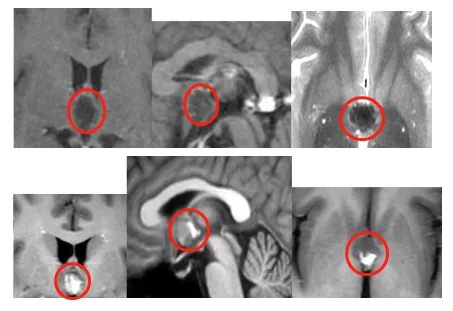

在神经外科领域,松果体区一直被称为手术的禁区。这里位于大脑最深处,血管神经错综复杂,每一步操作都如履薄冰。而海绵状血管瘤更是一种罕见的血管畸形,像一颗不定时炸弹,随时可能...

9岁的朋朋在半年来始终过的提心吊胆,她不得不提防着随时可能到来的癫痫,也必须忍受持续的头痛。然而,当父母带着她来到医院检查时,却被结果吓了一跳:脑中一个5cm大的海绵状血管瘤...

26岁,本该是人生肆意绽放的年纪,浩然却在结束高原行程后,被持续的头痛头晕拽入了人生转折的漩涡。 两个月的不适让他终于下定决心寻医,而核磁检查的结果,像一盆冷水浇透了他和家人...